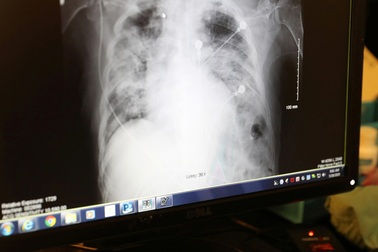

Những ca ghép phổi đặc biệt: Dấu ấn y học Việt Nam vươn tầm quốc tếGhép phổi từ người cho chết não là kỹ thuật khó của y học. Với 14 ca được thực hiện thành công, trong đó có những ca ghép đặc biệt, các bác sĩ Việt Nam đã viết nên câu chuyện hồi sinh kỳ diệu.

“Sốc” video phổi đen như than của người hút thuốcMột bác sĩ ghép tạng Trung Quốc đã chia sẻ đoạn video ghi lại cảnh lấy lá phổi màu đen từ cơ thể một người đàn ông hút thuốc lá 30 năm.

Hy vọng mới cho người cần ghép tạng: Nuôi cấy thành công phổi mớiCác nhà khoa học đã nuôi cấy được phổi của lợn từ tế bào của chính con vật trong phòng thí nghiệm.